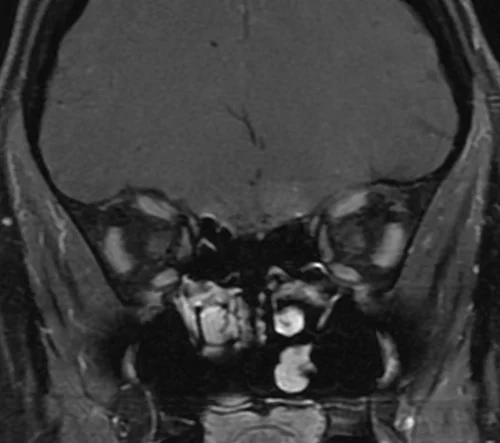

MRI Orbits coronal T1 fat sat images